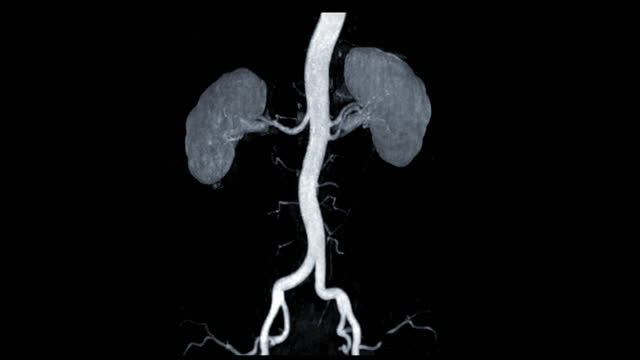

신장암은 흡연, 비만, 고혈압 등과 관련된 원인이 있을 수 있습니다. 그러나 암의 발생 원인을 규명하는 것보다 더 중요한 것은 조기 발견입니다. 신장암은 양쪽 신장에서 동시에 발견되는 경우가 드물며 대부분 한쪽에서 발견됩니다.

신장암은 혈액 검사나 소변 검사로는 조기 진단하기 어렵습니다. 따라서 건강을 유지하고자 하는 목적으로는 초음파 검사를 적어도 일 년에 한 번 받는 것이 좋습니다. 초음파 검사를 통해 작은 크기의 신장암도 조기에 발견할 수 있습니다.